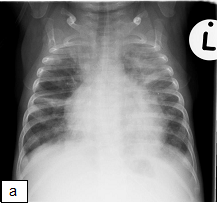

Figure 163a and b: (a) CXR taken pre-ART in a 4 month old child newly diagnosed with HIV infection. Xray shows: Multifocal airspace disease involving both upper lobes, right middle lobe, left lingular and left lower lobe. (b) CXR, 5 weeks post-ART initiation in the same child as above. He had been readmitted for worsening respiratory distress.

X-ray shows: Progressive air space disease with new more confluent left lower lobe, right lower lobe and right upper lobe consolidation plus a large pleural effusion with dense opacification of the left upper lobe as before.